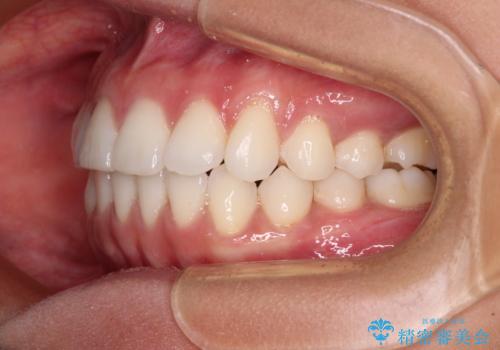

【モニター】インビザラインで口を閉じやすく

- 前に出ている上顎前歯が気になるとのことで来院された患者様です。

インビザラインを用い、IPR(歯と歯の間を削る)と歯列全体を後方に移動させることで、可能な限り前歯の突出感を改善することとしました。

元々の歯列も整っており、横顔の印象の出っ歯ではなかったため、仕上がりに満足できない可能性があると心配しておりましたが、口が閉じやすくなり、患者様には大変満足していただきました。